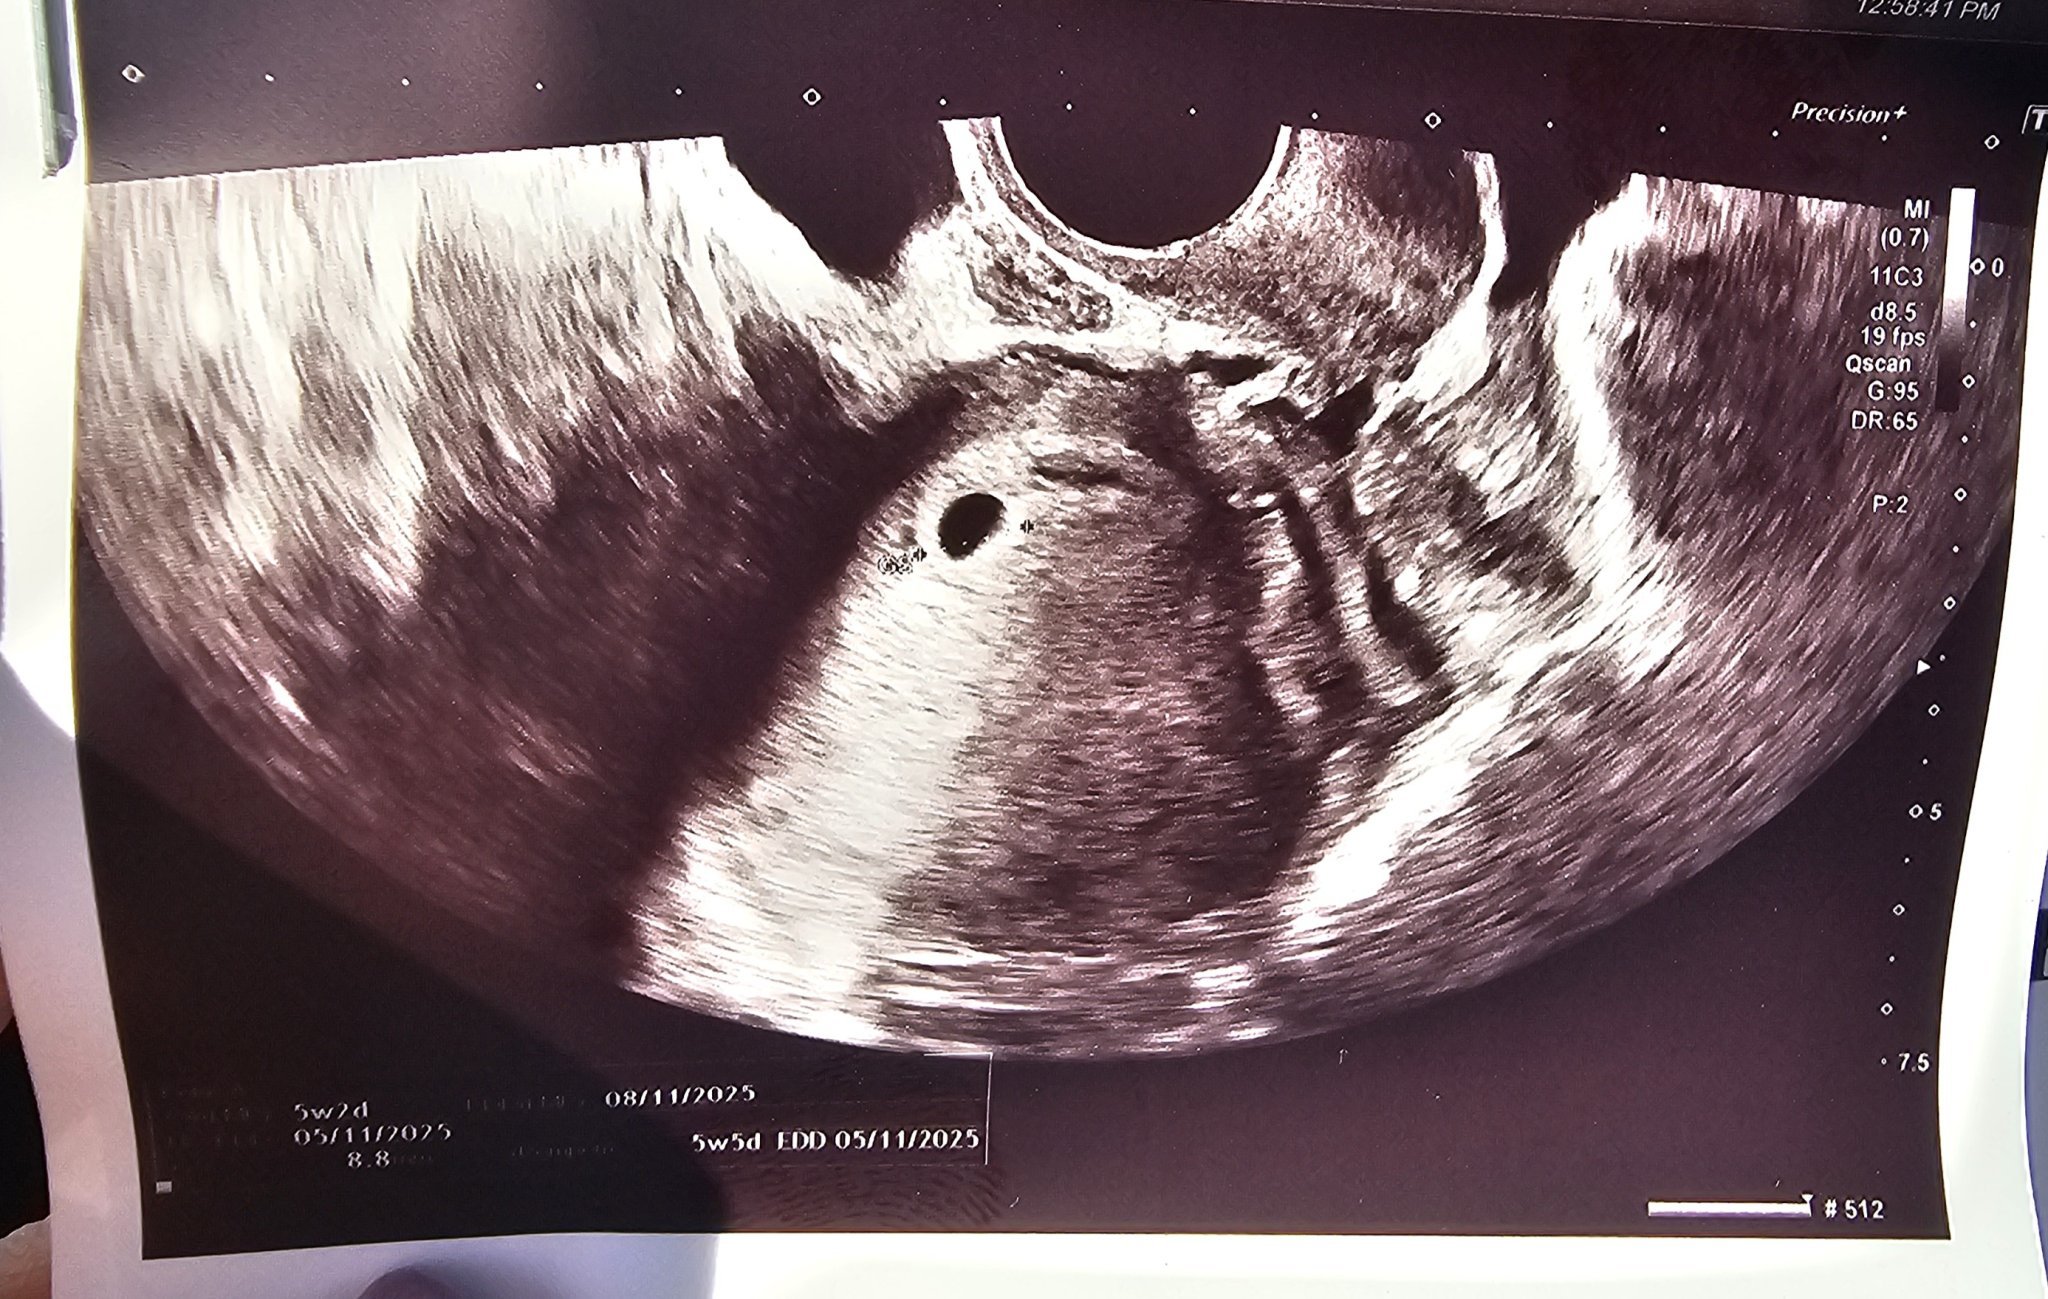

Какво представлява изображението от ехографията на 5-седмична и 2-дневна бременност?

Какво представляват белите точки в плодния сак на ехографската снимка?

Какво представлява изображението от ехографията на 5-седмична и 2-дневна бременност?

Какво представляват белите точки в плодния сак на ехографската снимка?

Какво представлява жълтото тяло на ехографската снимка?

Какво представляват черните точки в матката на ехографската снимка?